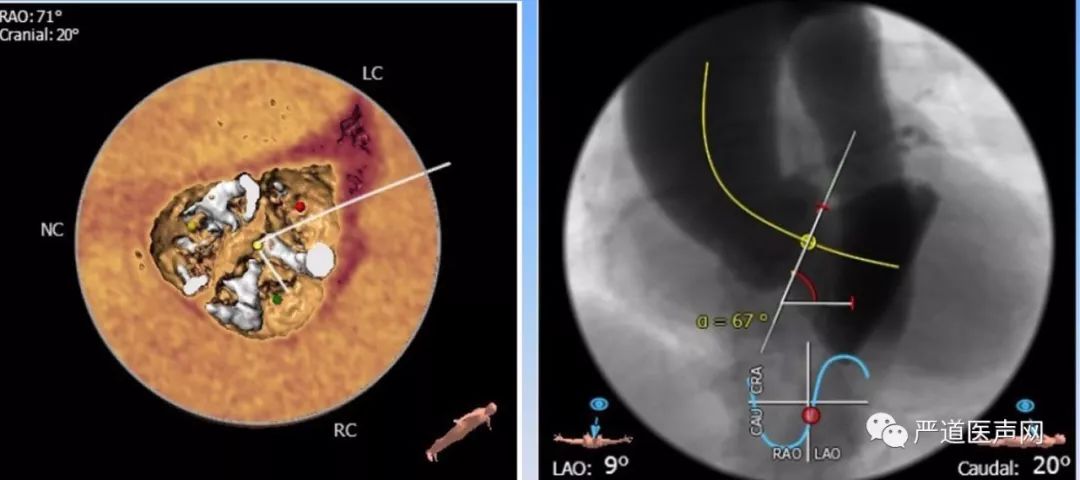

CTA提示患者瓣膜重度钙化,Type I型二叶主动脉瓣,横位心,主动脉与左心室夹角67°。(如下图)